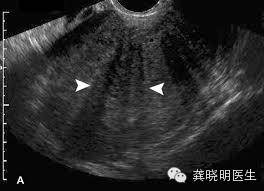

子宫肌腺症若是通过超声检查,往往可以发现子宫壁增厚,出现结构紊乱。

肌腺症在子宫内部若是局部形成一个象肌瘤一样的结节,在超声上可能会比较局限,看起来象是一个肌瘤,但是通常边界不如肌瘤清楚,绝大多数超声认为的腺肌瘤其实都是腺肌症的表现,这在核磁共振检查上更清晰。